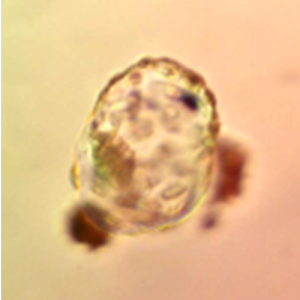

A human blastocyst that developed in SYNBIOS® SYNTHETIC EMBRYO CULTURE MEDIUM. Image was captured using the embryoscope. The workers noted that the performance of the SYNBIOS® SYNTHETIC EMBRYO CULTURE MEDIUM was comparable to contemporary conventional protein-containing medium. Courtesy: Yousef AlHelou, April 2020, Fakih IVF, United Arab Emirates.